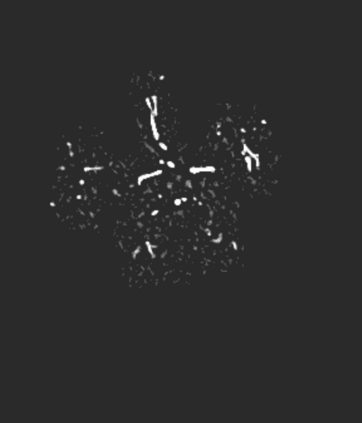

During the diagnosis of ischemic strokes, the Circle of Willis and its surrounding vessels are the arteries of interest. Their visualization in case of an acute stroke is often enabled by Computed Tomography Angiography (CTA). Still, the identification and analysis of the cerebral arteries remain time consuming in such scans due to a large number of peripheral vessels which may disturb the visual impression. In previous work we proposed VirtualDSA++, an algorithm designed to segment and label the cerebrovascular tree on CTA scans. Especially with stroke patients, labeling is a delicate procedure, as in the worst case whole hemispheres may not be present due to impeded perfusion. Hence, we extended the labeling mechanism for the cerebral arteries to identify occluded vessels. In the work at hand, we place the algorithm in a clinical context by evaluating the labeling and occlusion detection on stroke patients, where we have achieved labeling sensitivities comparable to other works between 92\,\% and 95\,\%. To the best of our knowledge, ours is the first work to address labeling and occlusion detection at once, whereby a sensitivity of 67\,\% and a specificity of 81\,\% were obtained for the latter. VirtualDSA++ also automatically segments and models the intracranial system, which we further used in a deep learning driven follow up work. We present the generic concept of iterative systematic search for pathways on all nodes of said model, which enables new interactive features. Exemplary, we derive in detail, firstly, the interactive planning of vascular interventions like the mechanical thrombectomy and secondly, the interactive suppression of vessel structures that are not of interest in diagnosing strokes (like veins). We discuss both features as well as further possibilities emerging from the proposed concept.